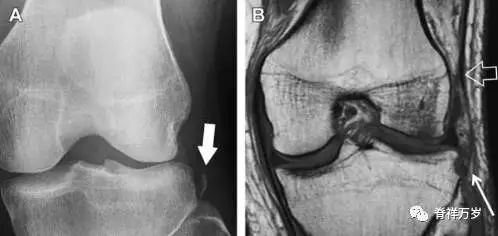

11Segond 骨折

Segond 骨折是发生在胫骨平台外侧的垂直撕脱性骨折(图 4)。这种骨折在前后位 X 线片上显示最佳。

屈曲位时膝关节受到内旋*力暴**作用,导致皮质骨撕脱性骨折,这种骨折常发生在运动员身上。常引起股骨内髁和胫骨平台后内侧骨挫伤,75%~100% 的患者伴前交叉韧带断裂,33% 的患者伴外侧半月板损伤。

图 4 一位足球运动员的 Segond 骨折

A 正位片示关节线下方胫骨外侧皮质撕脱(箭头)。B MRI 冠状位 T1 加权像示附着于髂胫带的骨折碎片(空箭头)。